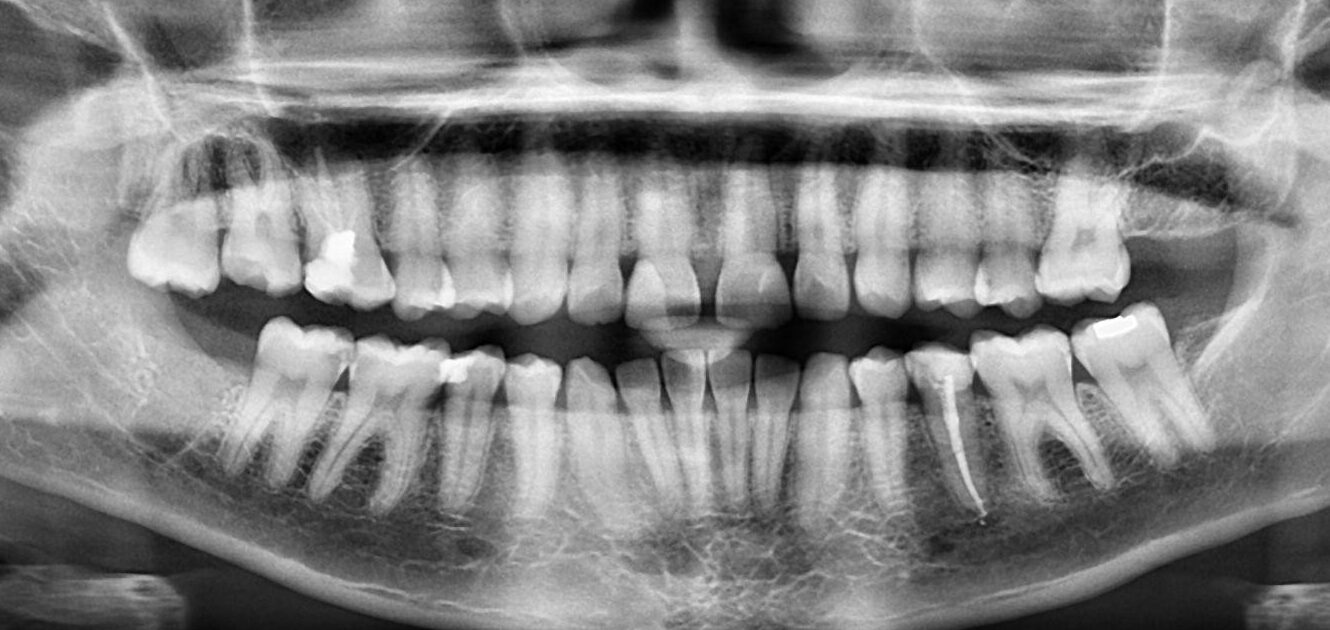

7. What option cannot be selected for the upper jaw of this panoramic X ray?

8. What option cannot be selected for the lower jaw of this panoramic X ray?

9. What option cannot be selected for this panoramic X ray?